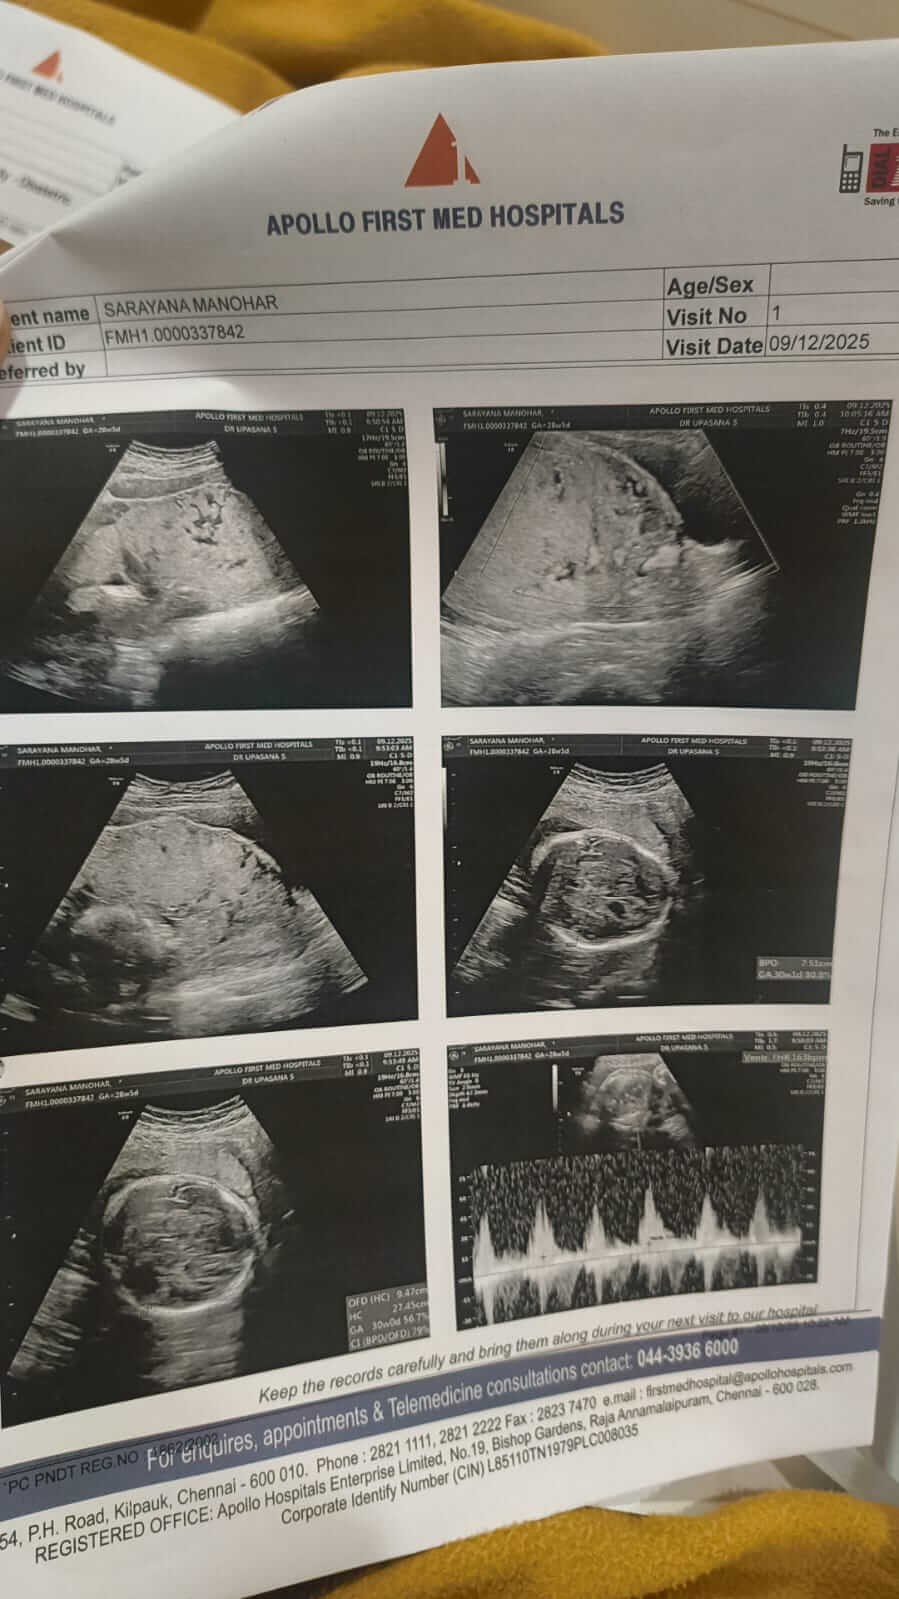

Saranya faced high-risk pregnancy complications and now, both my wife and my baby are fighting for their lives in the ICU.

What began as unbearable pain turned into an emergency surgery. I watched doctors rush her into the operating theatre, not knowing what was in store for my family. Our baby was born into machines, wires, and fear, taken straight into critical care. “They have to remain under strict medical observation and critical care,” said the doctors about my wife Saranya and our newborn baby.

Doctors have advised that both the mother and baby need continued ICU monitoring to survive.